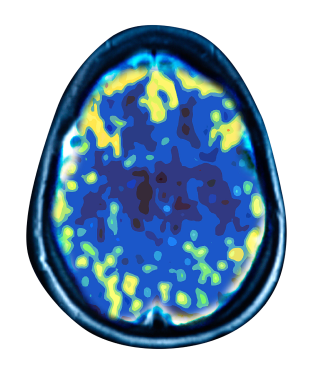

Treating depression at the source

Depressed Brain

Non Depressed Brain